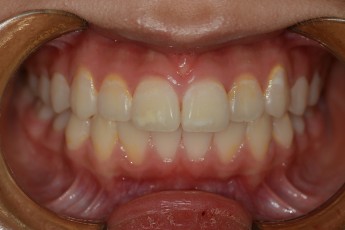

BEFORE & AFTER